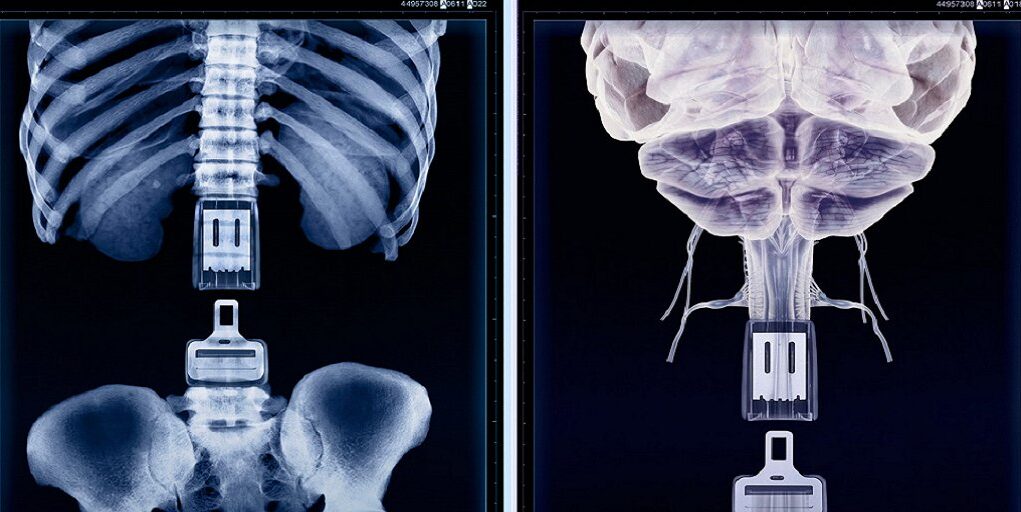

En España se registran cada año unos 150.000 siniestros viales con víctimas, de los que al menos un 20% tienen consecuencias en la columna vertebral. Quizá el daño o lesión más conocido y común es el latigazo cervical. Pero el más temido y respetado es, con toda seguridad, la paraplejia.

En 2023, ultimo año con datos completos, además de 1.806 fallecidos, casi 125.000 personas resultaron heridas, de las que 9.265 sufrieron daños graves que requirieron hospitalización. Y de estos heridos graves, 8.140 sufrieron traumatismo craneoencefálico, unas 6.406 daños graves en la columna y más de 400 quedaron con la médula espinal seriamente afectada.

Su trabajo se ha convertido en referencia internacional por un enfoque muy concreto: cirugía mínimamente invasiva de columna (MISS), apoyada en endoscopia, abordajes tubulares, neuronavegación y robótica, para reducir daño quirúrgico y acelerar recuperación. En sus propias explicaciones, estas técnicas buscan menos ingreso, menos dolor, menor riesgo de infección y menos tiempo de recuperación frente a la cirugía abierta clásica.

La lesión medular: la vida no termina, pero cambia de golpe

En la intervención del Dr Parajón en el programa Seguridad Vial en Radio 5, el foco se repetía: la lesión medular es una de las consecuencias más temidas porque no afecta solo a la movilidad. Puede comprometer autonomía, trabajo, relaciones, salud mental. Y obliga a reconstruir la vida con un “antes y después”.

Una lesión vertebral o medular puede llegar por un siniestro de tráfico, sí. Pero también por una caída, un accidente doméstico o un impacto deportivo. La biomecánica es la misma: fuerzas, velocidad, fragilidad humana.